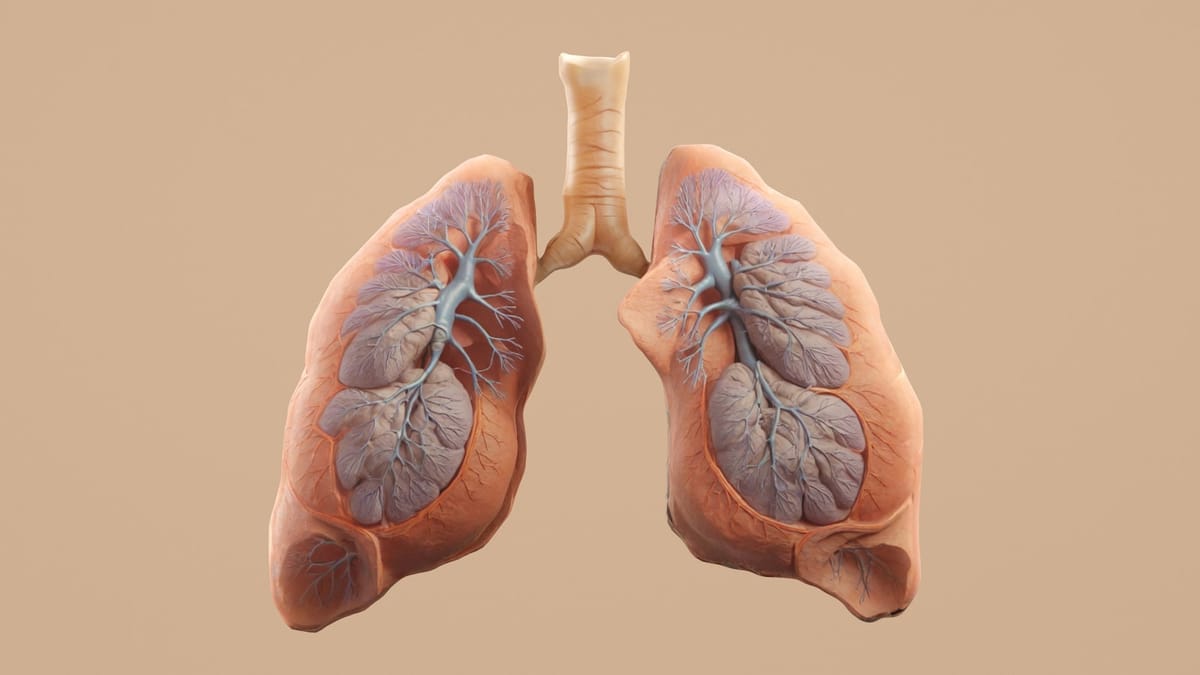

- Pulmonálna embólia (PE): Veľká krvná zrazenina v pľúcniciach blokuje prietok krvi a zvyšuje tlak v pľúcach.